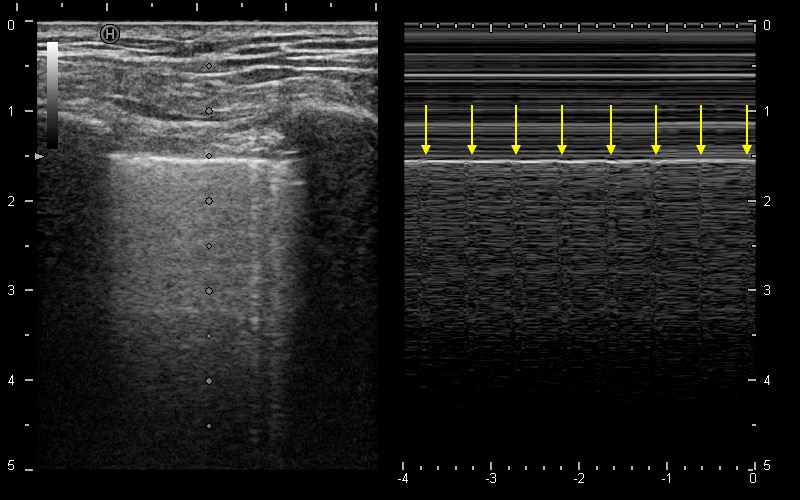

呼吸困難。みられる所見はなにか?

Lung pulse sign

肺エコーにおいて、Lung slidingの消失は気胸の除外に有用な感度の高い所見であるが、一方で特異度はやや低い。胸膜癒着や換気量低下、無呼吸状態ではLung slidingは目立たないこともあるが、心拍動が肺を伝って壁側胸膜を律動的に揺らす結果、Mモードで等間隔の縦縞模様を形成する。この所見がLung pulse signであり、心臓とプローブ下の壁側胸膜の間に空気の層が存在しない、すなわち気胸がないことを示す所見である。(関連動画:#95)